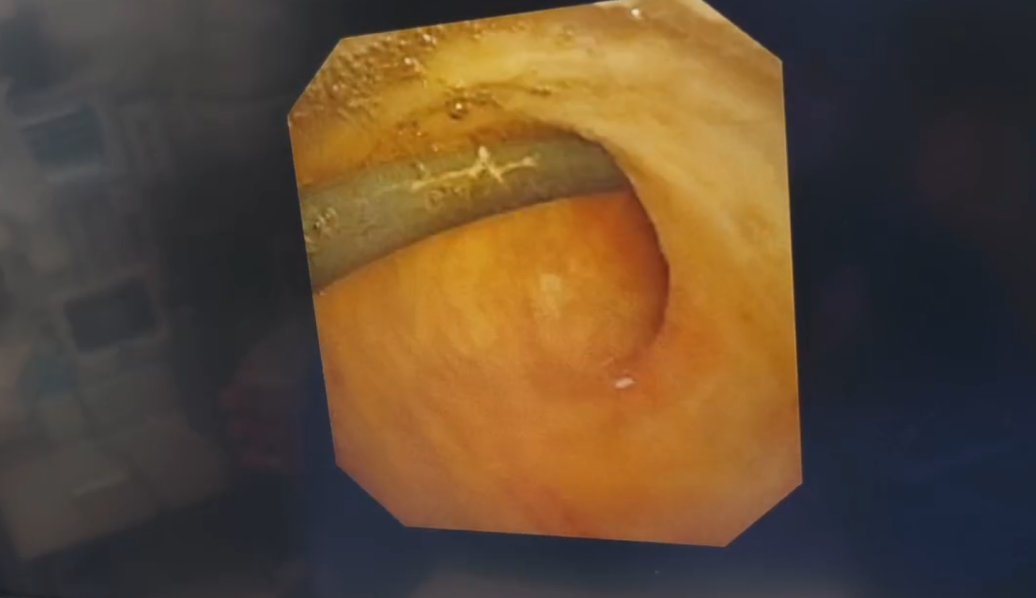

图2:胆道镜视野下胆总管多发的结石